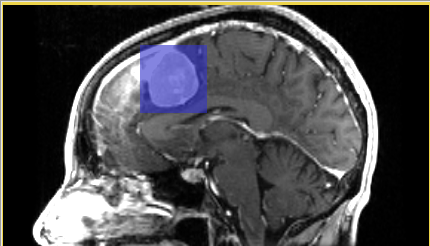

• Step 2: Define volume of interest

Use mouse pointer in combination with left button clicks to identify the bounding box enclosing pathology in three projections of the viewer. You can also use the mouse to adjust sliders defining the bounding box more precisely. If you made a mistake, click "Reset" button to start over.

ChangeTracker Step2 1.png ChangeTracker Step2 2.png